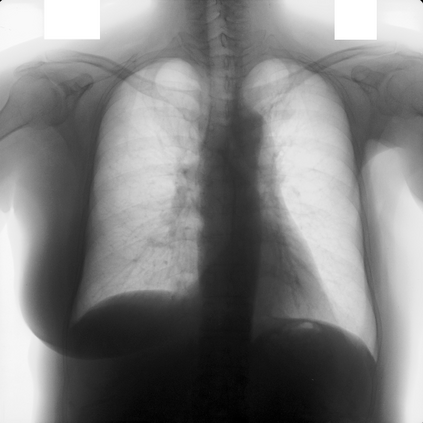

Multi-organ segmentation of X-ray images is of fundamental importance for computer aided diagnosis systems. However, the most advanced semantic segmentation methods rely on deep learning and require a huge amount of labeled images, which are rarely available due to both the high cost of human resources and the time required for labeling. In this paper, we present a novel multi-stage generation algorithm based on Generative Adversarial Networks (GANs) that can produce synthetic images along with their semantic labels and can be used for data augmentation. The main feature of the method is that, unlike other approaches, generation occurs in several stages, which simplifies the procedure and allows it to be used on very small datasets. The method has been evaluated on the segmentation of chest radiographic images, showing promising results. The multistage approach achieves state-of-the-art and, when very few images are used to train the GANs, outperforms the corresponding single-stage approach.